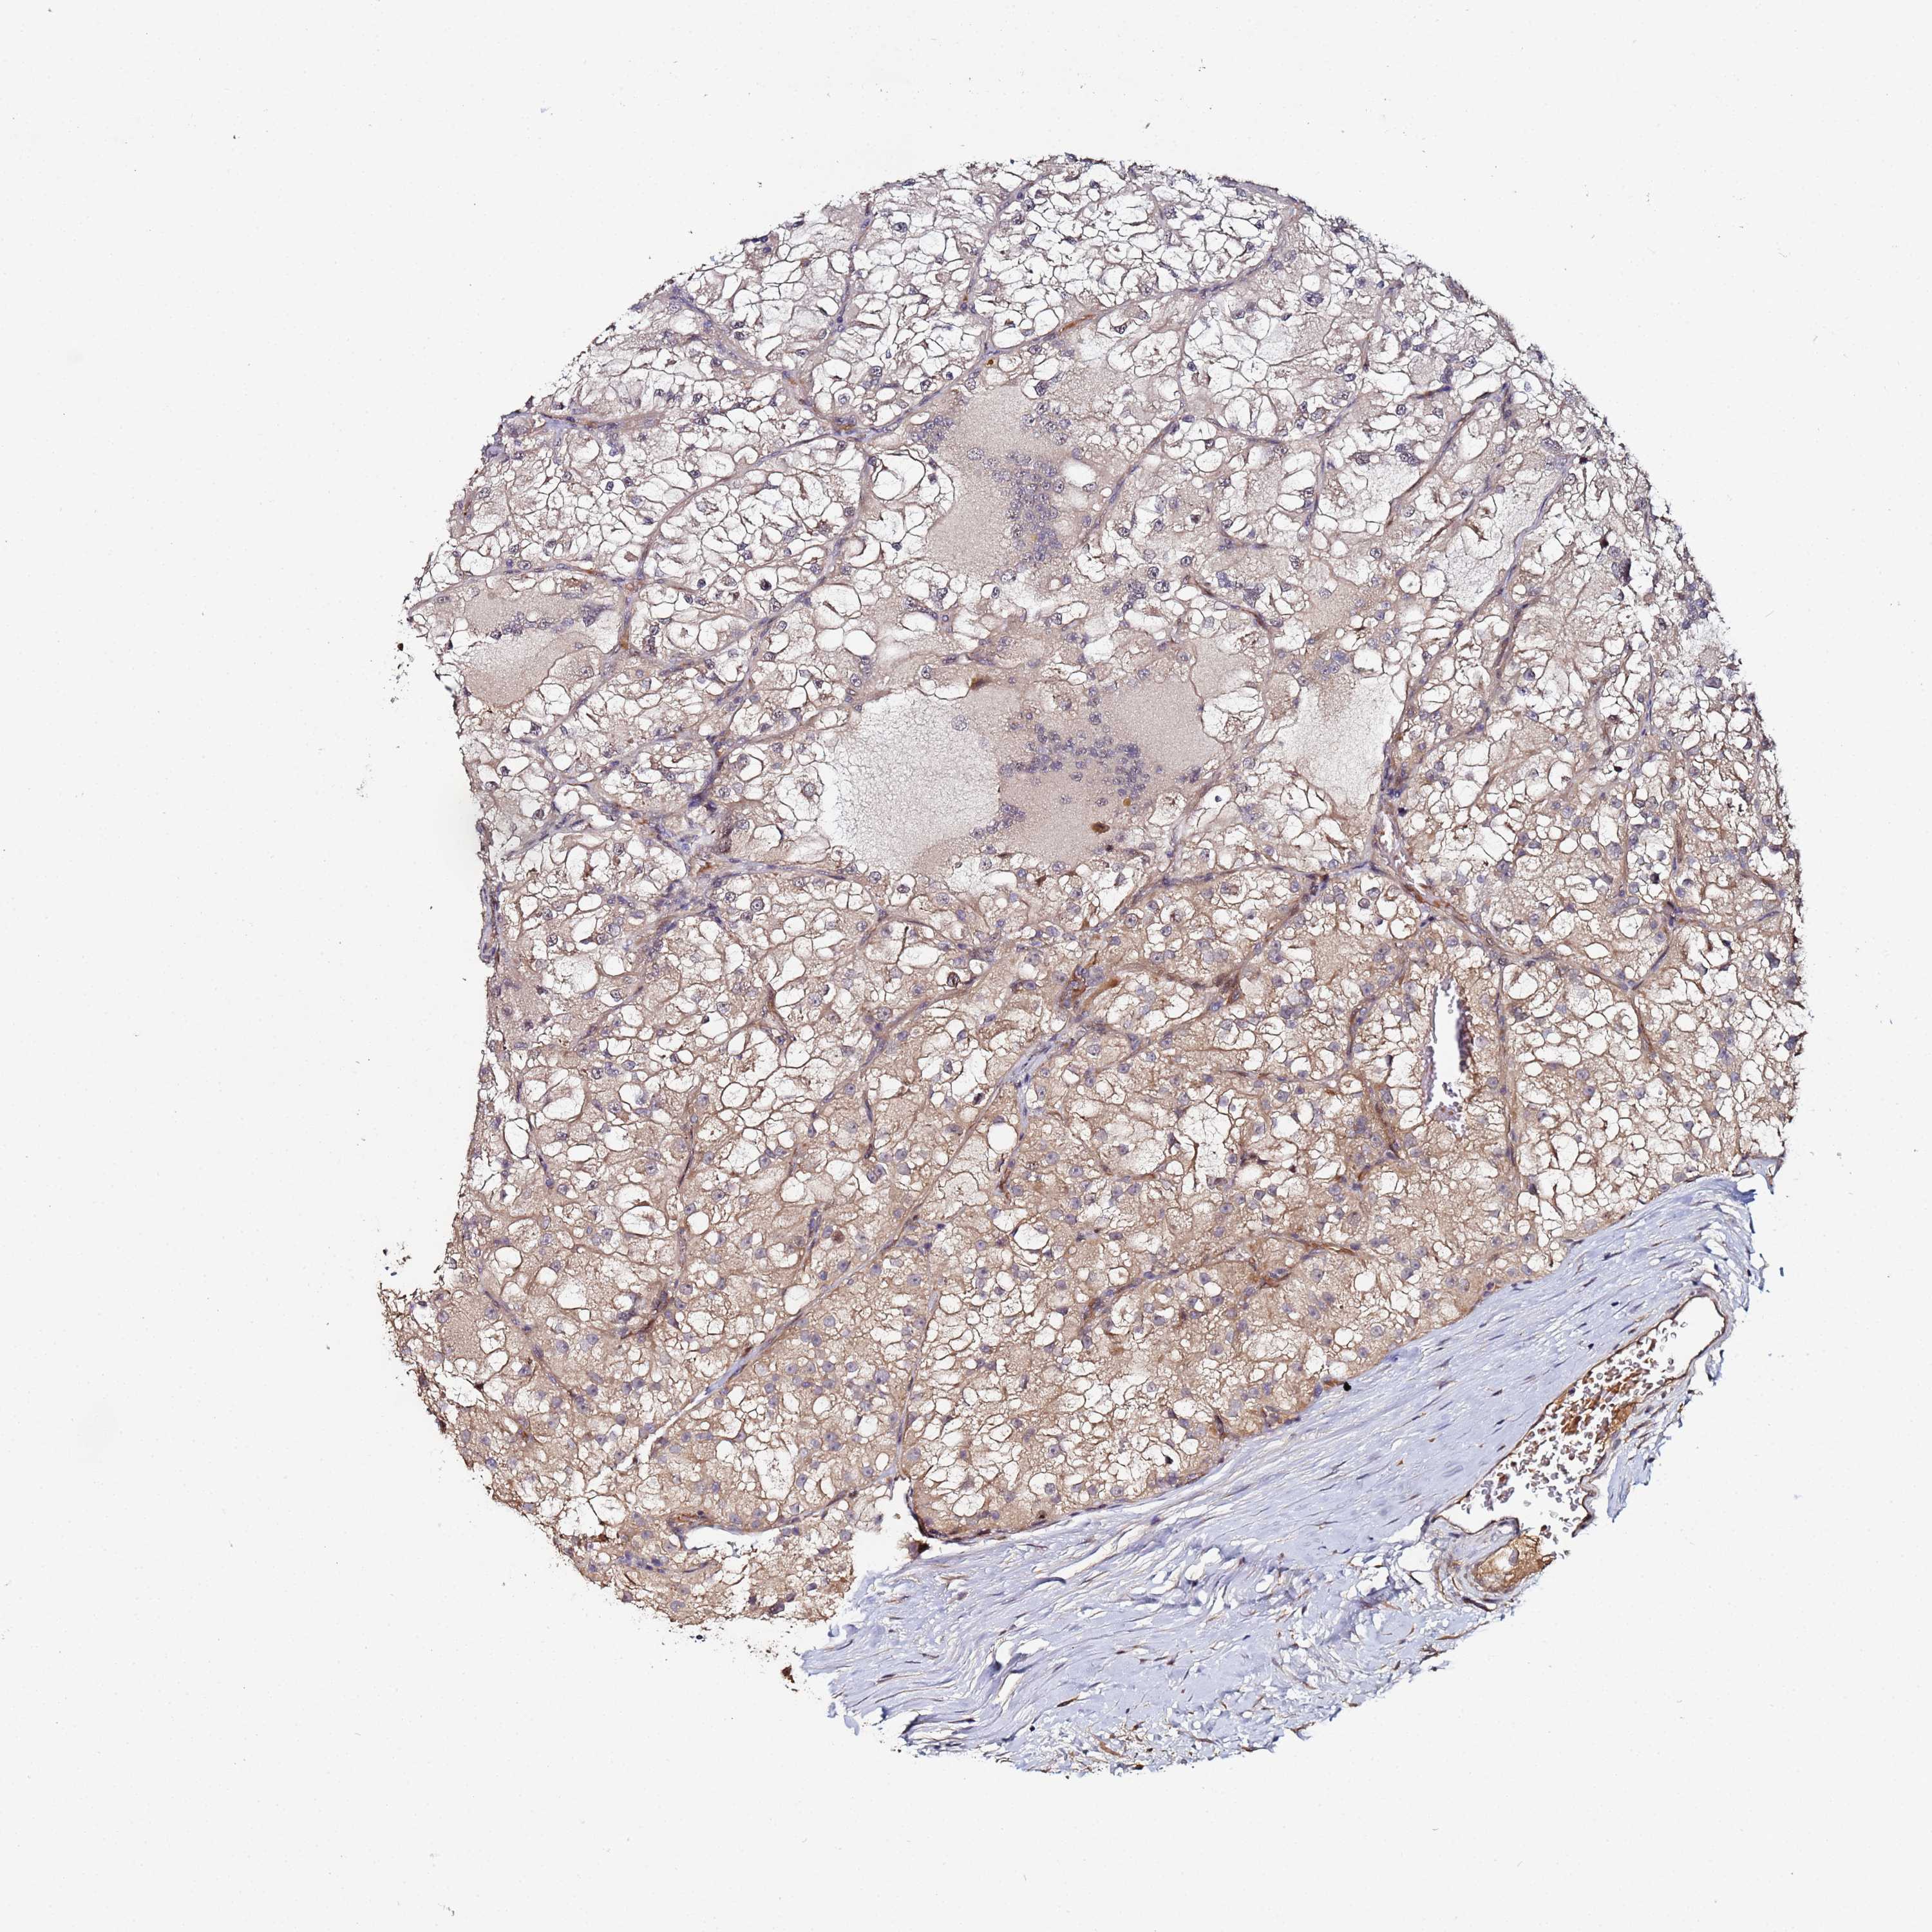

KIDNEY RENAL CLEAR CELL CARCINOMA (VALIDATION) - Interactive survival scatter ploti

The Survival Scatter plot shows the clinical status (i.e. dead or alive) for all individuals in the patient cohort, based on the same data that underlies the corresponding Kaplan-Meier plots. Patients that are alive at last time for follow-up are shown in blue and patients who have died during the study are shown in red.

The x-axis shows the expression levels (FPKM) of the investigated gene in the tumor tissue at the time of diagnosis. The y-axis shows the follow-up time after diagnosis (years). Both axes are complimented with kernel density curves demonstrating the data density over the axes. The top density plot shows the expression levels (FPKM) distribution among dead (red) and alive patients (blue). The right density plot shows the data density of the survived years of dead patients with high and low expression levels respectively, stratified using the cutoff indicated by the vertical dashed line through the Survival Scatter plot. This cutoff is automatically defined based on the FPKM cutoff that minimizes the p-score. The cutoff can be changed by dragging the vertical line or by entering a cutoff value in the square labeled "Current cut-off".

Under the Survival Scatter plot the p-score landscape (black curve; left axis) is shown together with dead median separation (red curve; right axis). Dead median separation is the difference in median mRNA expression between patients who have died with high and low expression, respectively. It is calculated as follows: median FPKM expression of dead patients with high expression - median FPKM expression of dead patients with low expression. This is intended to aid the user in visually exploring custom cutoffs and the associated p-scores and dead median separation.

Individual patient data is displayed and can be filtered by clicking on one or more of the category buttons on the top of the page. Categories describing expression level and patient information include: high, low, alive, dead, female, male and tumor stages. The scale of the x-axis can be toggled between linear and log-scale by clicking on the "x log" button. Mouse-over function shows TCGA ID, patient information and mRNA expression (FPKM) for each patient.

& Survival analysisi

Kaplan-Meier plots summarize results from analysis of correlation between mRNA expression level and patient survival. Patients were divided based on level of expression into one of the two groups "low" (under cut off) or "high" (over cut off). X-axis shows time for survival (years) and y-axis shows the probability of survival, where 1.0 corresponds to 100 percent.

OSER1 is not prognostic in Kidney Renal Clear Cell Carcinoma (validation)

Best expression cut offi

Based on the FPKM value of each gene, patients were classified into two groups and association between prognosis (survival) and gene expression (FPKM) was examined. The best expression cut-off refers the FPKM value that yields maximal difference with regard to survival between the two groups at the lowest log-rank P-value. Best expression cut-off was selected based on survival analysis .

When clicking on this number, the vertical dashed line indicating cut-off, the interactive survival plot, and the Kaplan-Meier curve will be adjusted to show results based on the best expression cut-off.

: 38

TCGA RNA samplesi

RNA-seq data is reported as average FPKM (number Fragments Per Kilobase of exon per Million reads), generated by the The Cancer Genome Atlas (TCGA) .

Normal distribution across the dataset is visualized with box plots, shown as median and 25th and 75th percentiles. Points are displayed as outliers if they are above or below 1.5 times the interquartile range. FPKM values of the individual samples are presented next to the box plot.

Average pTPM 44.7

Number of samples 100